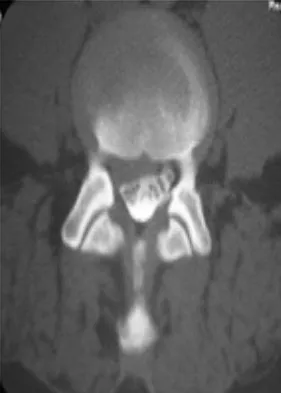

A 46-year-old woman who was involved in a motor vehicle accident reports a 4-month history of right-sided lower back pain and pain radiating into the right thigh. The patient underwent an extensive 3-month course of physical therapy and now is dependent on narcotic medication for pain control. Epidural injection therapy has failed to improve her symptoms. Examination is significant for weakness of hip flexion in the seated position and for decreased sensation to light touch in the medial anterior thigh region. Straight leg raise is negative, but the femoral stretch test reproduces anterior thigh pain. A CT myelogram image, at L3-L4, is shown in Figure 3. What is the most appropriate management at this time?

Figures 29a and 29b show the radiograph and CT scan of a 48-year-old man who has diffuse spinal pain. What is the most likely diagnosis?